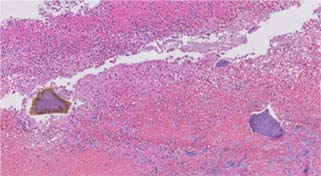

Figure 2: Low power image of colonic mucosa with fibrinopurulent exudate and crystals (Hematoxylin and eosin, 2× magnification).

Figure 3: Medium power image of colonic mucosa with fibrinopurulent exudate and crystals (Hematoxylin and eosin, 5× magnification).